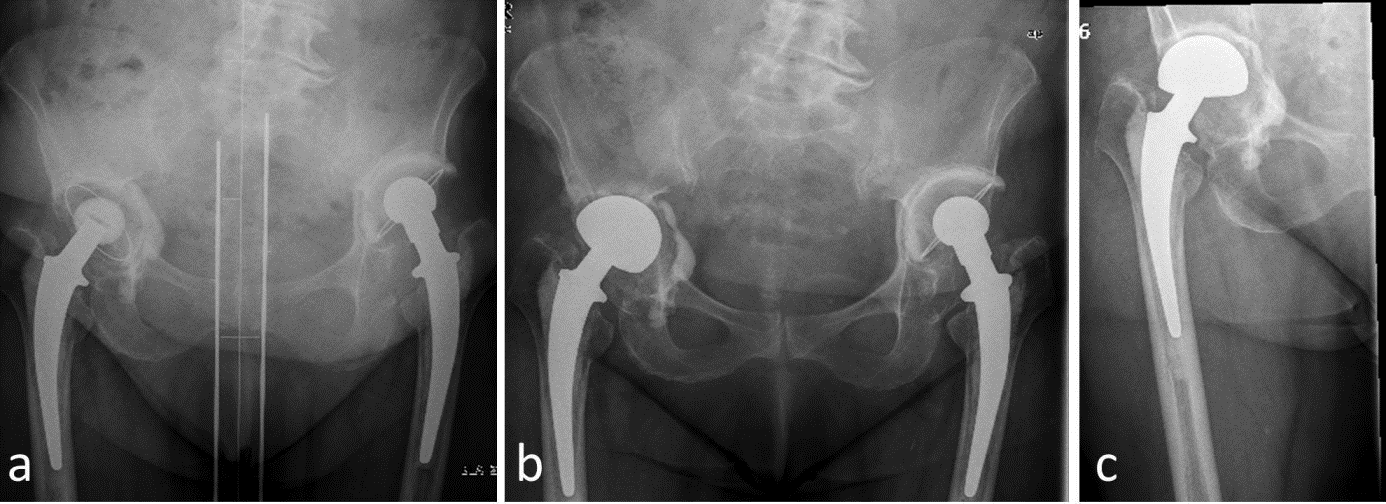

Figure1: 72-year-old patient, ASA 3, intraoperative significant acetabular bone defects. Uncomplicated postoperative course. Improvement of the Harris Hip Score from 39 preoperatively to 74 two years after revision surgery.

a. aseptic loosening of the acetabular cup, b. immediate postoperative result, c. two years after surgery